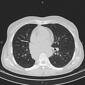

Chest pain, breath shortness, cough and hemoptysis

Pulmonology

Very Difficult

CT Scan

axial lung

axial non-contrast